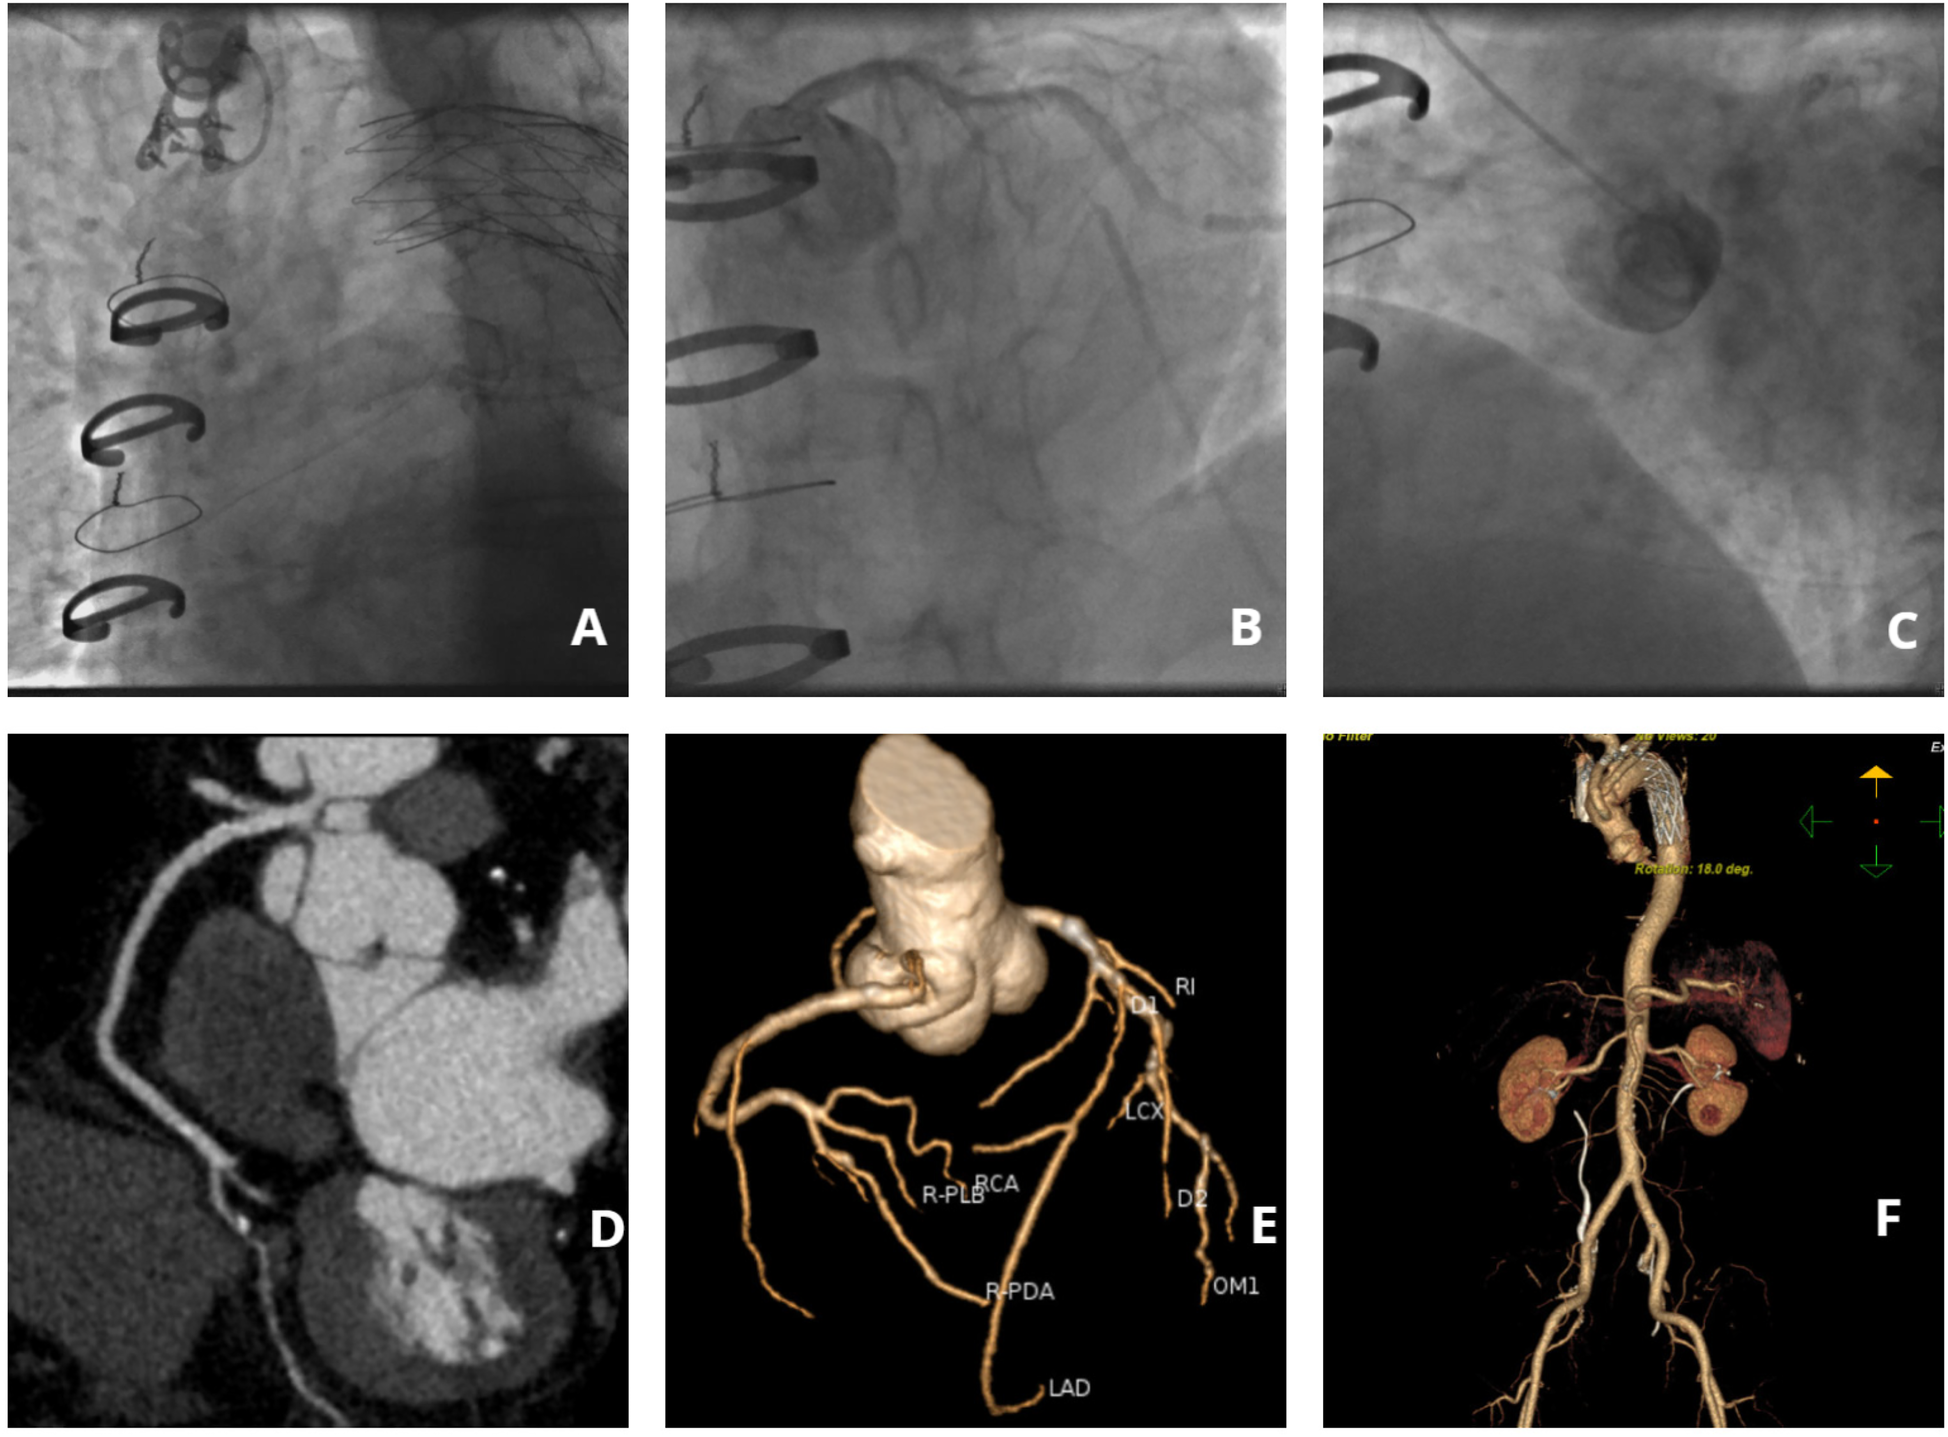

Following a comprehensive diagnostic evaluation excluding aortic dissection recurrence, emergency coronary angiography was performed after obtaining informed consent within 60 min of hospital admission. Due to the patient's complex vascular surgical history and absence of recent aortic imaging studies, right radial arterial access was strategically selected to minimize procedural risks. The angiographic procedure encountered significant technical challenges: (1) severe tortuosity of the brachiocephalic trunk substantially impeded catheter manipulation, (2) only selective left coronary angiography could be successfully performed, and (3) right coronary artery visualization required a non-selective contrast injection through a pigtail catheter (Figure 1). Key angiographic findings included: Complete occlusion of the proximal left anterior descending artery (LAD) with developed collateral circulation; Critical 90% stenosis of the distal left circumflex artery (LCX) with preserved TIMI 3 flow; Suboptimal but patent right coronary artery (RCA) visualization. The procedure was ultimately discontinued following multidisciplinary consultation, based on: Resolution of ischemic symptoms; Prolonged procedural duration (Contrast agent volume: 300 ml; Radiation dose: 3,000 mSv.); Acceptable angiographic visualization of critical lesions.

Figure 1

Imaging findings of coronary and aortic vasculature. (A) Angiographic visualization of brachiocephalic trunk tortuosity; (B) Selective angiography of the left coronary artery; (C) Non-selective right coronary angiography performed via pigtail catheter; (D) Computed tomography angiography (CTA) of the right coronary artery; (E) Coronary CTA; (F) Aortic CTA.

On postoperative day 5, coronary computed tomography angiography (CTA) revealed the following vascular abnormalities: Complete occlusion of the mid left anterior descending artery (LAD) with established collateral circulation; Severe stenosis (≥90%) of the distal left circumflex artery (LCX); Non-significant stenosis (<50%) of the right coronary artery (RCA). Concurrent aortic CTA demonstrated characteristic postoperative anatomical alterations, including: Saccular protrusion of the aortic root; Crescent-shaped periaortic hypodensity, suggestive of either chronic dissection remnant or organized intramural hematoma (Figure 1). Following comprehensive cardiothoracic surgical consultation, the following determinations were made: Clear indication for coronary artery bypass grafting (CABG) based on angiographic findings; Contraindication for immediate surgical intervention due to extensive pleural adhesions from previous aortic surgery; Recommendation for referral to the original surgical center for specialized management. Detailed vascular access assessment identified: Prohibitive catheter navigation challenges via radial approach due to extreme vascular tortuosity; Significant risk of iatrogenic false lumen entry with femoral approach. Based on these findings, the patient was transferred to the original tertiary surgical institution for definitive management.